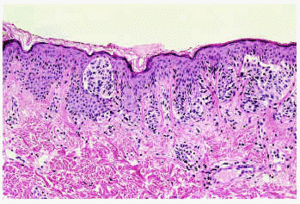

Fig. 3.--Imagen histopatológica de un corte del sector estable (E). Nevus melanocítico compuesto de predominio intradérmico sin atipia. Se aprecia algún pequeño quiste córneo en la epidermis (imágenes puntuales brillantes tipo pseudoquistes de milio en la dermoscopia).

Una mujer de 17 años con múltiples nevus melanocíticos, algunos clínicamente atípicos, seguía revisiones periódicas con objeto de detectar de forma precoz la presencia de lesiones pigmentadas nuevas y/o cambiantes de aspecto problemático. Para facilitar su seguimiento se tomaron fotografías basales (cámara Polaroid Macro 5 SRL) en septiembre de 1999 a la edad de 15 años. En un control efectuado en enero de 2001 se detectó un crecimiento focal en una lesión situada en la espalda (fig. 1). El examen dermoscópico reveló una imagen con dos componentes lesionales bien definidos (fig. 2). El sector correspondiente a la zona estable (E) mostró un patrón relativamente homogéneo no atípico, con algunos glóbulos marrones dispersos, telangiectasias y algunos puntos claros brillantes (pseudoquistes de milio). En conjunto, este examen era compatible con un nevus compuesto o intradérmico. El sector correspondiente a la zona inestable en crecimiento (C) mostró un patrón marcadamente diferente, destacando su asimetría estructural en dos ejes, un área de tonalidad ligeramente azulada y otro área (correspondiente al frente de crecimiento de la lesión) mostrando una imagen de RPN (fig. 2). En el diagnóstico diferencial se planteó la posibilidad de melanoma incipiente y se procedió a su extirpación. El estudio histológico del área con dermoscopia no atípica, que no había mostrado cambios durante el seguimiento clínico (sector E), correspondía a un nevus compuesto, con predominio del componente intradérmico (fig. 3). En la epidermis se apreciaban pequeñas formaciones quísticas de queratina que justificaban el hallazgo dermoscópico de puntos claros brillantes (pseudoquistes de milio). El área con imagen dermoscópica atípica que había crecido en los meses previos (sector C) mostraba un nevus melanocítico compuesto con un componente juntural prominente, con atipia arquitectural pero sin atipia citológica (fig. 4). En su porción central se observaron algunos melanófagos en la dermis, lo que podía contribuir a generar el área azulada en la imagen dermoscópica (fig. 2). La atipia arquitectural y la disposición de las tecas, algunas de gran tamaño, serían el sustrato morfopatológico del RPN en este caso.